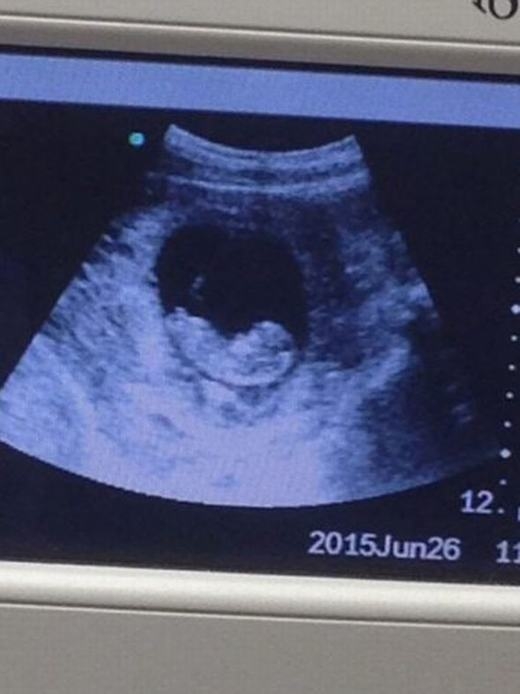

Hình ảnh siêu âm của người phụ nữ này đã khiến nhiều người dựng tóc gáy. Trong ảnh siêu âm là hình ảnh “quỷ dữ” xuất hiện bên cạnh thai nhi. Tuy nhiên các chuyên gia cho rằng đây chỉ là một ảo giác quang học.

Nếu nhìn lướt qua, có thể nhiều người nghĩ đây là một bức ảnh siêu âm bình thường như bao ảnh siêu âm khác. (Ảnh: Express)

Theo tờ báo nổi tiếng của Anh Express mô tả, hình ảnh siêu âm có thể bình thường khi mới nhìn vào với thai nhi trong bào thai. Nhưng nếu quan sát kĩ hơn, nhất là ở góc phải, ta sẽ thấy hình ảnh của một người khác với khuôn mặt dữ tợn đang nhìn vào thai nhi.

Bức hình siêu âm này sau đó được đăng tải lên Imgur với chú thích: “Hình ảnh siêu âm thai nhi của một người bạn. Bạn thấy gì khi nhìn vào?”.

Cận cảnh hình ảnh siêu âm. (Ảnh: Express)

Với nội dung rùng rợn này, bức ảnh lập tức được phát tán một cách chóng mặt. Liên tiếp các bình luận được đưa ra. “Tôi thấy một con quỷ bên phải”, tài khoản Blind bình luận. “Không, nữ thần Hindu mới đúng chứ!”, bạnLizzie cho biết. “Ủa sao tôi không thấy con quỷ nào nhỉ? Một nàng tiên cá thân thiện mà!”, một người khác phản bác.

Các nhà khoa học cũng đã lập tức vào cuộc sau đó. Theo như lí giải, đây thực chất chỉ là một dạng ảo ảnh quang học mang tên Pareidolia (ảo giác khuôn mặt). Khi đó, trí não con người có xu hướng gán những hình mẫu quen thuộc với hình dạng hoặc âm thanh ngẫu nhiên. Đây cũng là lời giải thích cho việc vì sao ta hay nhìn thấy hình mặt người, con cua... trên sao Hỏa.

Trước đó, cũng đã có khá nhiều bức ảnh siêu âm kì lạ và cũng không kém phần thú vị, ví như thai nhi hình mặt quỷ, thai nhi có đầu hình trái tim, hình nhân vật quỷ Emperor Palpatine trong bộ phim Star Wars...